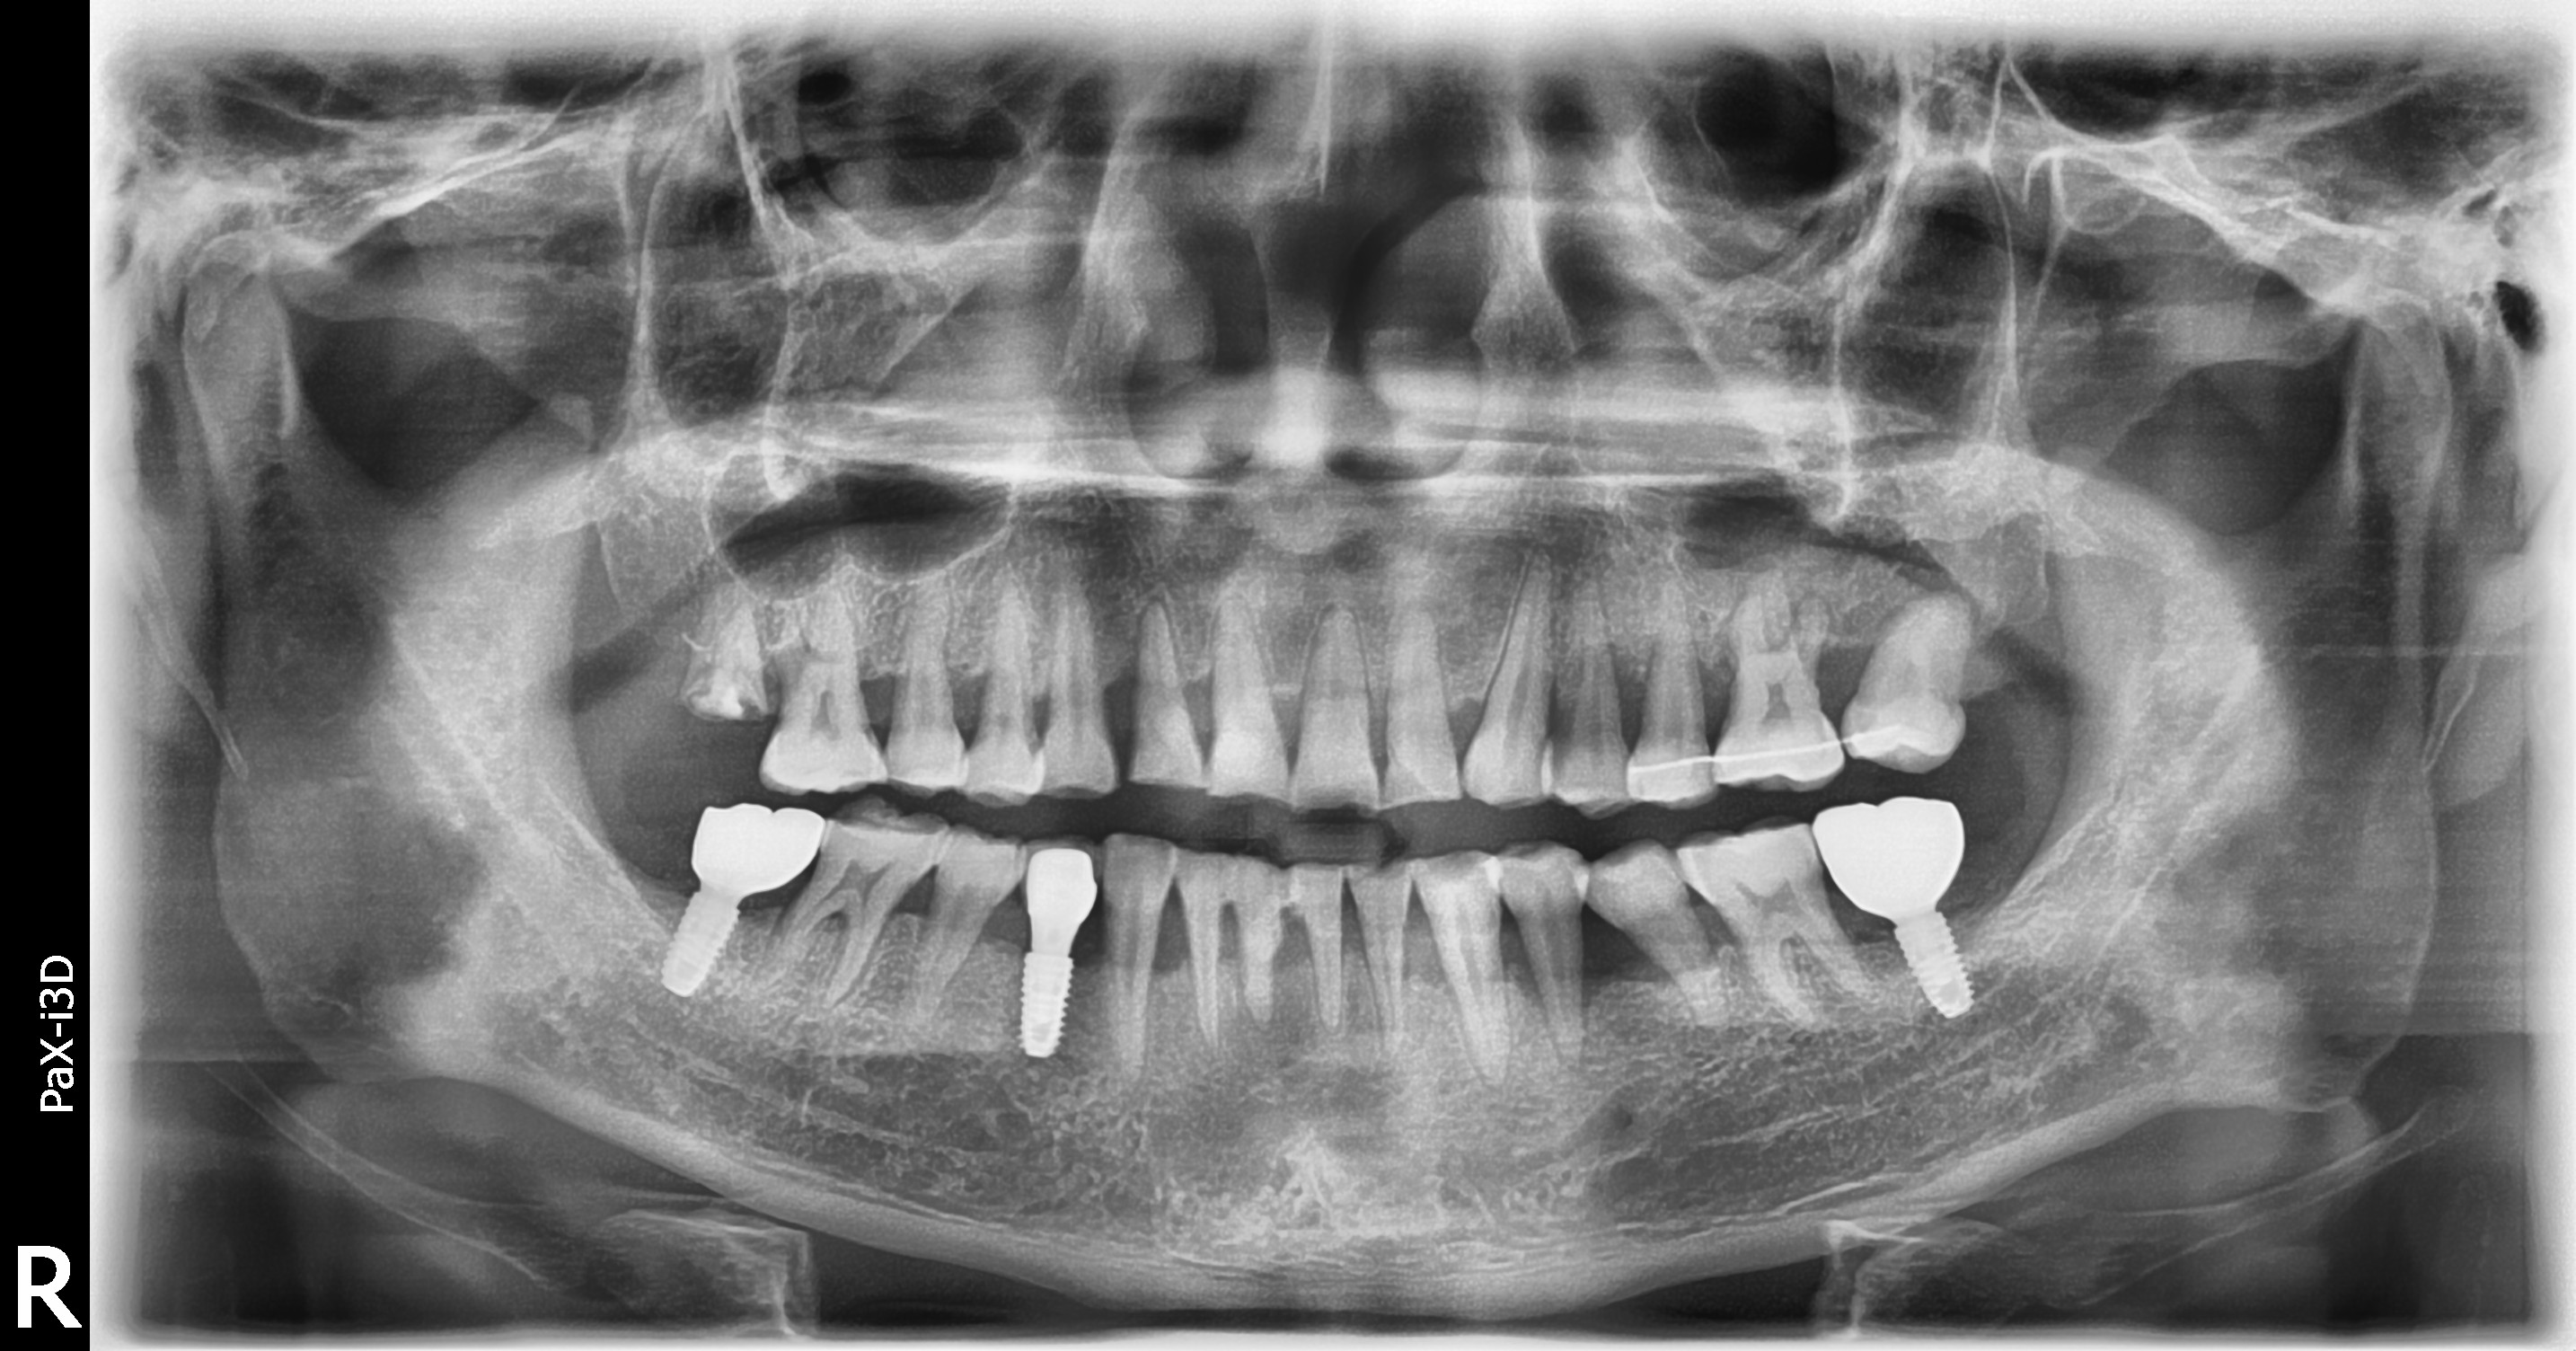

임플란트/틀니